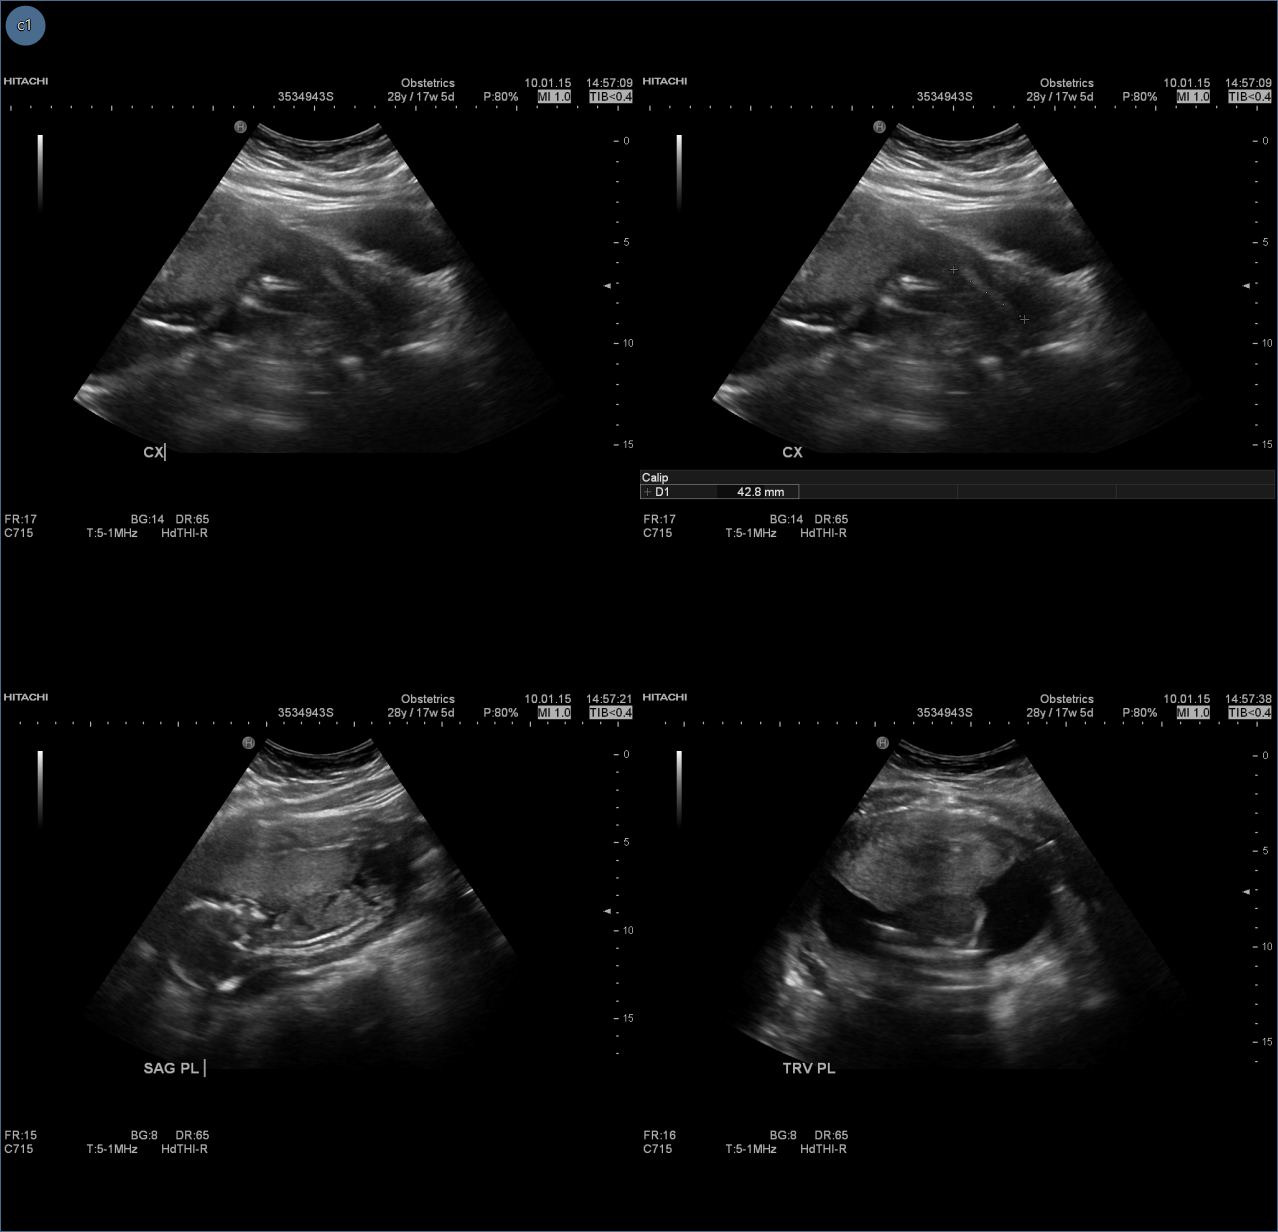

The selected image frame will now show images in the series as 2 x 2 tiles within the frame.